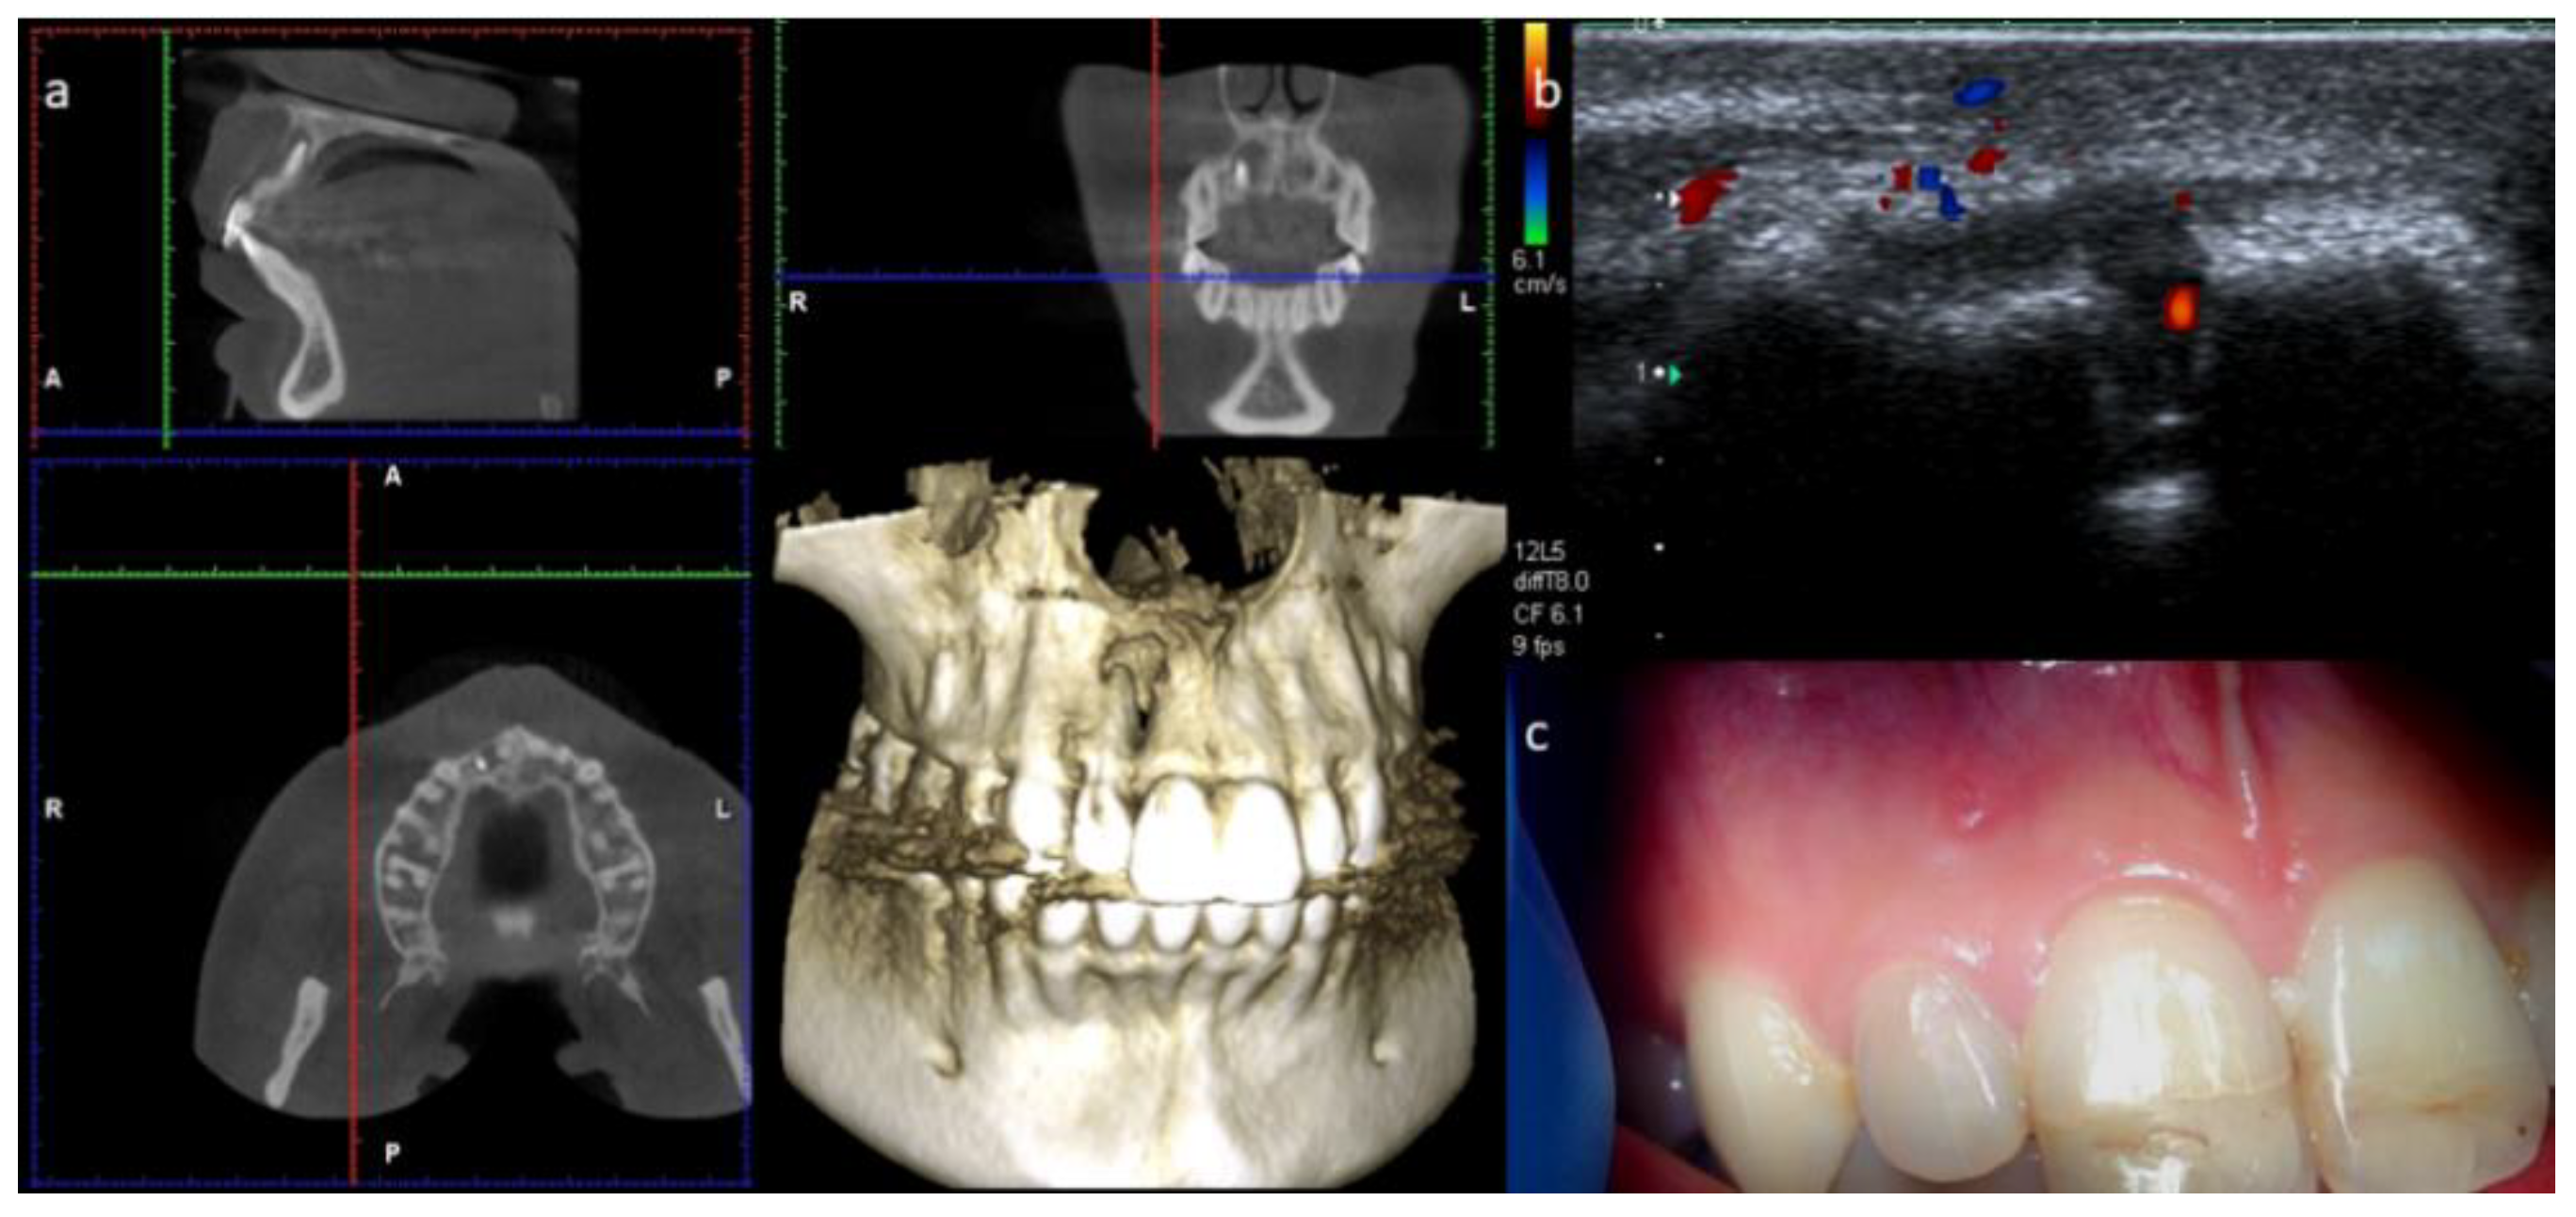

2. Case Report